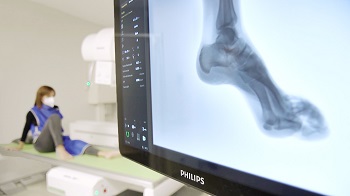

Asepeyo ha instalado, en su centro asistencial Barcelona-Vía Augusta, un sistema de fluoroscopia con control remoto combinado con radiografía digital avanzada, el CombiDiagnost R90 1.1 de Philips. El equipo permite abarcar estudios, tanto de radiología simple como de radiología compleja, en una misma sala, ofreciendo más comodidad y seguridad al paciente. Esta nueva release 1.1 del equipo Philips, es la primera que se instala a nivel global.

Con el CombiDiagnost R90 1.1, cuya instalación es la primera que se realiza en todo el mundo, el profesional sanitario puede controlar remotamente la geometría del equipo, adaptándola a la posición del paciente. “Con este sistema no necesitamos mover al paciente, que en principio con una lesión sufre más dolor, por lo que le ayudamos mucho”, destaca la enfermera, Susana Estecha, una de las encargadas de la adquisición de diagnósticos.

Las funciones de radiología digital del equipo Philips permiten a Asepeyo la realización de diagnósticos fiables con alta calidad de imagen. Como señala el doctor Vázquez, la tecnología digital “nos permite una mejor calidad de imagen, mayor rapidez, la conservación de los estudios en un formato digital y, por tanto, es un avance muy importante en la calidad asistencial que perseguimos”.

“Esta tecnología es muy útil porque podemos conseguir varias proyecciones con un importante ahorro de radiación para el paciente, y nos aporta un diagnóstico mucho más fiable”, apunta la enfermera Estecha. Esto se debe a que el sistema permite gestionar las dosis de radiación, una herramienta de la que se benefician tanto los pacientes, como el personal sanitario.